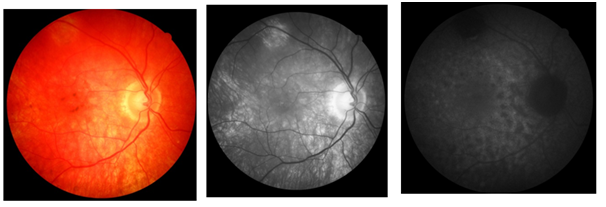

Laboratory tests showed the following results: complete blood count without changes, serology for non-reactive HIV, VDRL 1/128, toxoplasmosis IgG positive (185.0) and IgM negative (0.43), serologies for hepatitis B and C negative, FAN negative and negative rheumatoid factor. Ultrasonography was then performed in both eyes, which showed the presence of multiple pockets of serous retinal detachment with a macula glued to the right eye; and multiple pockets of serous retinal detachment, with macular edema in the left eye. With the diagnosis of Vogt-Koyanagi-Harada syndrome closed, treatment with oral prednisone 1 mg / kg was initiated, in addition to maintaining 1% prednisolone eye drops at weekly weaning. Two weeks after the beginning of oral immunosuppressive therapy, there was an improvement in visual acuity, which presented, with correction, in DO, 20/30 and in LEFT EYE, 20/40; in addition to reduction of retinal edema. Intraocular pressure using Goldmann's tonometry, OD 24mmHg and LEFT EYE 26mmHg, and associated brimonidine eye drops with timolol of 12 / 12h in both eyes (BE). In subsequent consultations, the patient presented negative VDRL after treatment for syphilis and control of intraocular pressure using hypotensive eye drops. Slow weaning from oral prednisone was carried out over the course of a year and maintained at 20 mg / day with stabilization of visual acuity at 20/20, with correction, in both eyes. One year after the onset of the condition, the patient presented to the retinography the presence of a "sunset" image in the right eye (Figure 3a) and in the left eye (Figure 3b)  Angiography showed the presence of hyperfluorescent lesions due to a window defect, due to the mobilization area and atrophy of the retinal pigment epithelium, seen during the examination, both in the left eye (Figure 5a) and in the right eye (Figure 5b). In an attempt to completely withdraw oral medication with slow weaning, visual loss of three lines was observed in the Snellen table in RIGHT EYE (20/40) and LEFT EYE remained stable at 20/20. Thus, a dose of 20 mg/ day of oral prednisone was maintained for two months, with slow weaning to 5 mg/ day, but again there was a worsening of VA (RIGHT EYE: 20/40 and LEFT EYE: 20/30). Thus, it was decided to suspend oral prednisone at 20mg / day and start injectable treatment with adalimumab. The patient is waiting for the medication to be released by the Unified Health System.

Figure 3a Retinography of the right eye.

Figure 3b Retinography of the left eye.